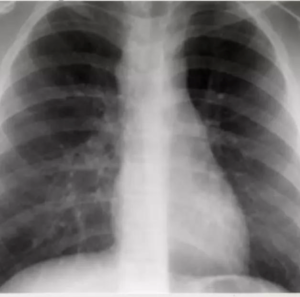

• Miliary TB refers to widespread dissemination of TB by hematogenous spread.

• Seen more frequently in reactivation TB.

The characteristic radiographic and high-resolution CT findings consist of innumerable, 1- to 3-mm diameter nodules randomly distributed throughout both lungs